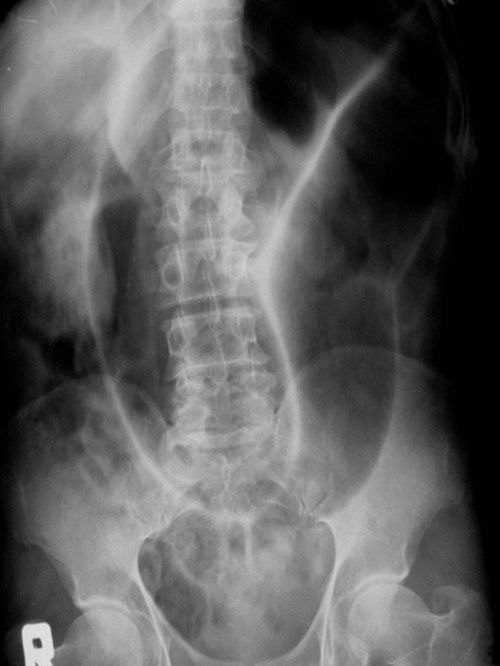

What does this AXR show?

You can see the typical ‘coffee bean’ appearance with three dense lines converging towards the site of obstruction (Frimann Dahl’s sign) in keeping with sigmoid volvulus.